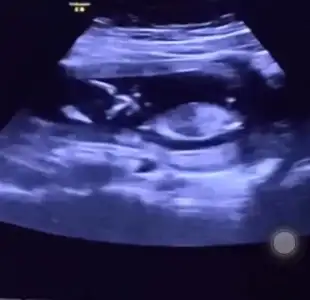

banada yorum yaparmısınız amine hanımBence kız canım. Sağlıklı gelsin inşallah![]()

Bence kızbanada bakarmısınız![]()

Kıza benziyorbanada bakarmısınız![]()

diğer fotoğrafa göre yorumladımbanada bakarmısınız![]()